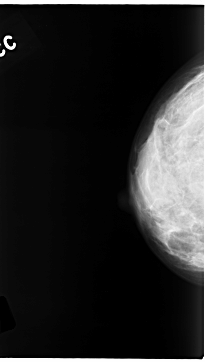

C_0139_1.RIGHT_CC

RIGHT_CC LINES 4696 PIXELS_PER_LINE 2664 BITS_PER_PIXEL 12 RESOLUTION 50 NON_OVERLAY